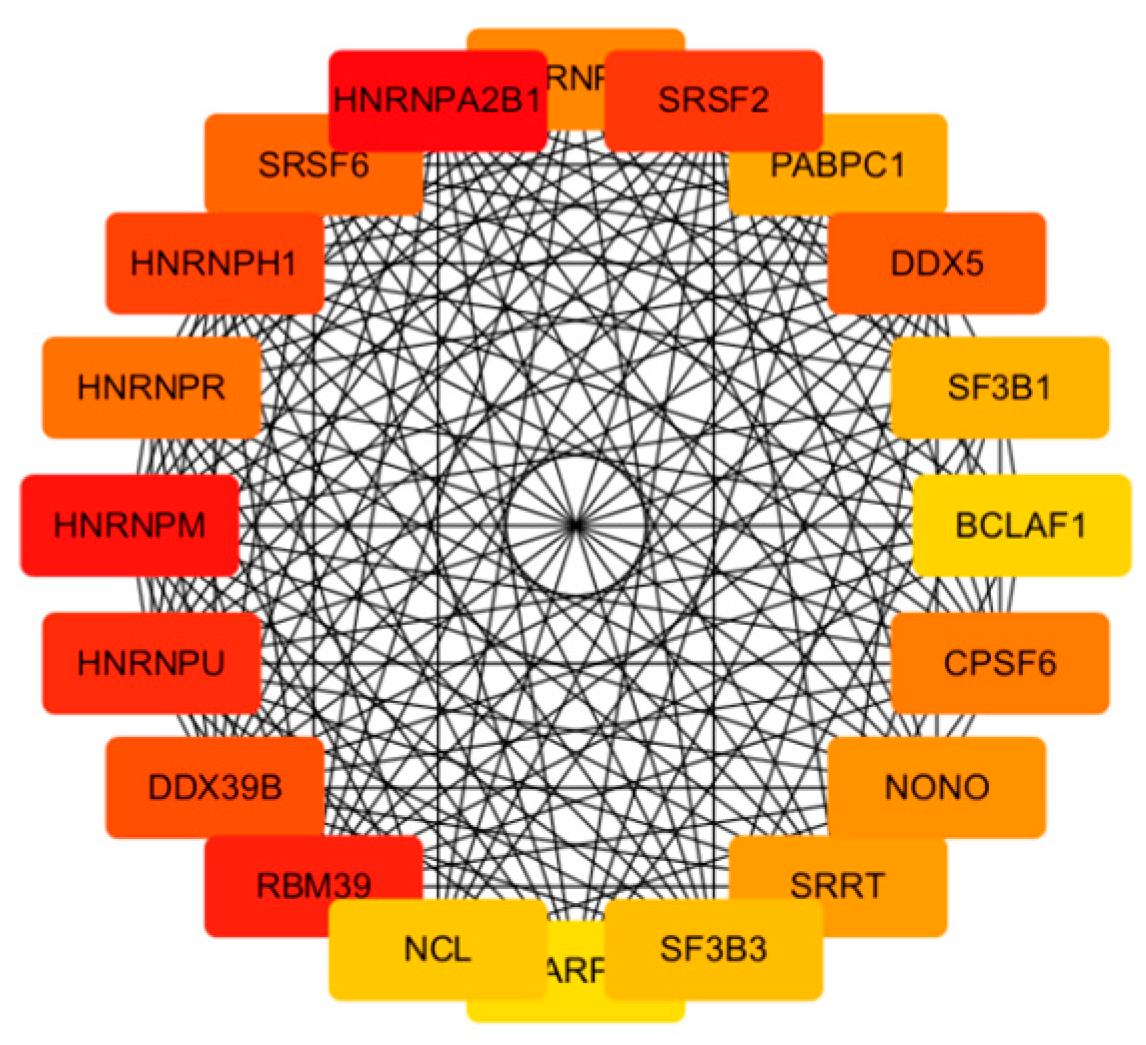

Central to our findings are the hub genes HNRNPA2B1, HNRNPM, and RBM39, identified through the protein–protein interaction (PPI) network analysis as key regulators of acne pathogenesis. HNRNPA2B1, a heterogeneous nuclear ribonucleoprotein, modulates RNA splicing and stability, and its upregulation in infected keratinocytes may enhance the expression of pro-inflammatory transcripts, such as those encoding cytokines like IL-6 [

22]. This is consistent with our observation of significantly elevated IL-6 levels (

p < 0.01), a cytokine known to promote keratinocyte proliferation and sebocyte differentiation in acne [

23]. HNRNPM, involved in alternative splicing, likely contributes to follicular hyper-keratinization by dysregulating genes associated with keratinocyte differentiation, a hallmark of comedogenesis. Similarly, RBM39, a splicing factor interacting with U2AF65, may amplify inflammatory signaling by modulating C-JUN phosphorylation, mimicking pathogen-associated molecular patterns (PAMPs) that activate innate immunity [

24]. These hub genes collectively regulate sebaceous gland inflammation, immune cell recruitment, and epidermal proliferation, positioning them as promising biomarkers for acne severity and potential therapeutic targets. For instance, elevated HNRNPA2B1 expression could serve as a diagnostic indicator in acne lesions, enabling personalized interventions targeting RNA processing pathways [

20].

10]. The significant increase in IL-6 secretion validates the transcriptomic upregulation of IL-6 signaling and aligns with hub gene functions, as HNRNPA2B1 and RBM39 regulate cytokine expression through splicing [

22]. These findings highlight IL-6 as a pivotal mediator of acne inflammation, suggesting that targeting its upstream regulators or CLR signaling could mitigate

C. acnes IA

1–induced damage. Furthermore, the cutaneous microenvironment and its extracellular matrix (ECM) components play a crucial role in modulating inflammatory responses to microbial stimuli, such as